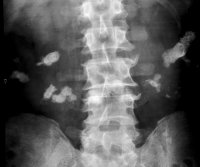

Die Hufeisenniere neigt aufgrund ihrer morphologischen Verhältnisse zu Harnstau, Harnwegsinfekt und daraus resultierend zur Harnsteinbildung, die zu erheblichen Komplikationen führen kann, wie in dieser Kasuistik gezeigt.

Der Patient kam mit Zeichen eines schweren, fieberhaften Harnwegsinfektes in unsere Behandlung. Die Diagnostik mit Sonographie und Ausscheidungsurogramm sowie Angiographie ergab eine ausgedehnte Harnsteinbildung beiderseits, wobei es im linken Nierenanteil zu Harnabflussbehinderungen gekommen war. Die Abbildungen zeigen die diagnostischen Maßnahmen. Der linke Nierenanteil wurde wegen erheblichen pyonephrotischem Umbau entfernt.